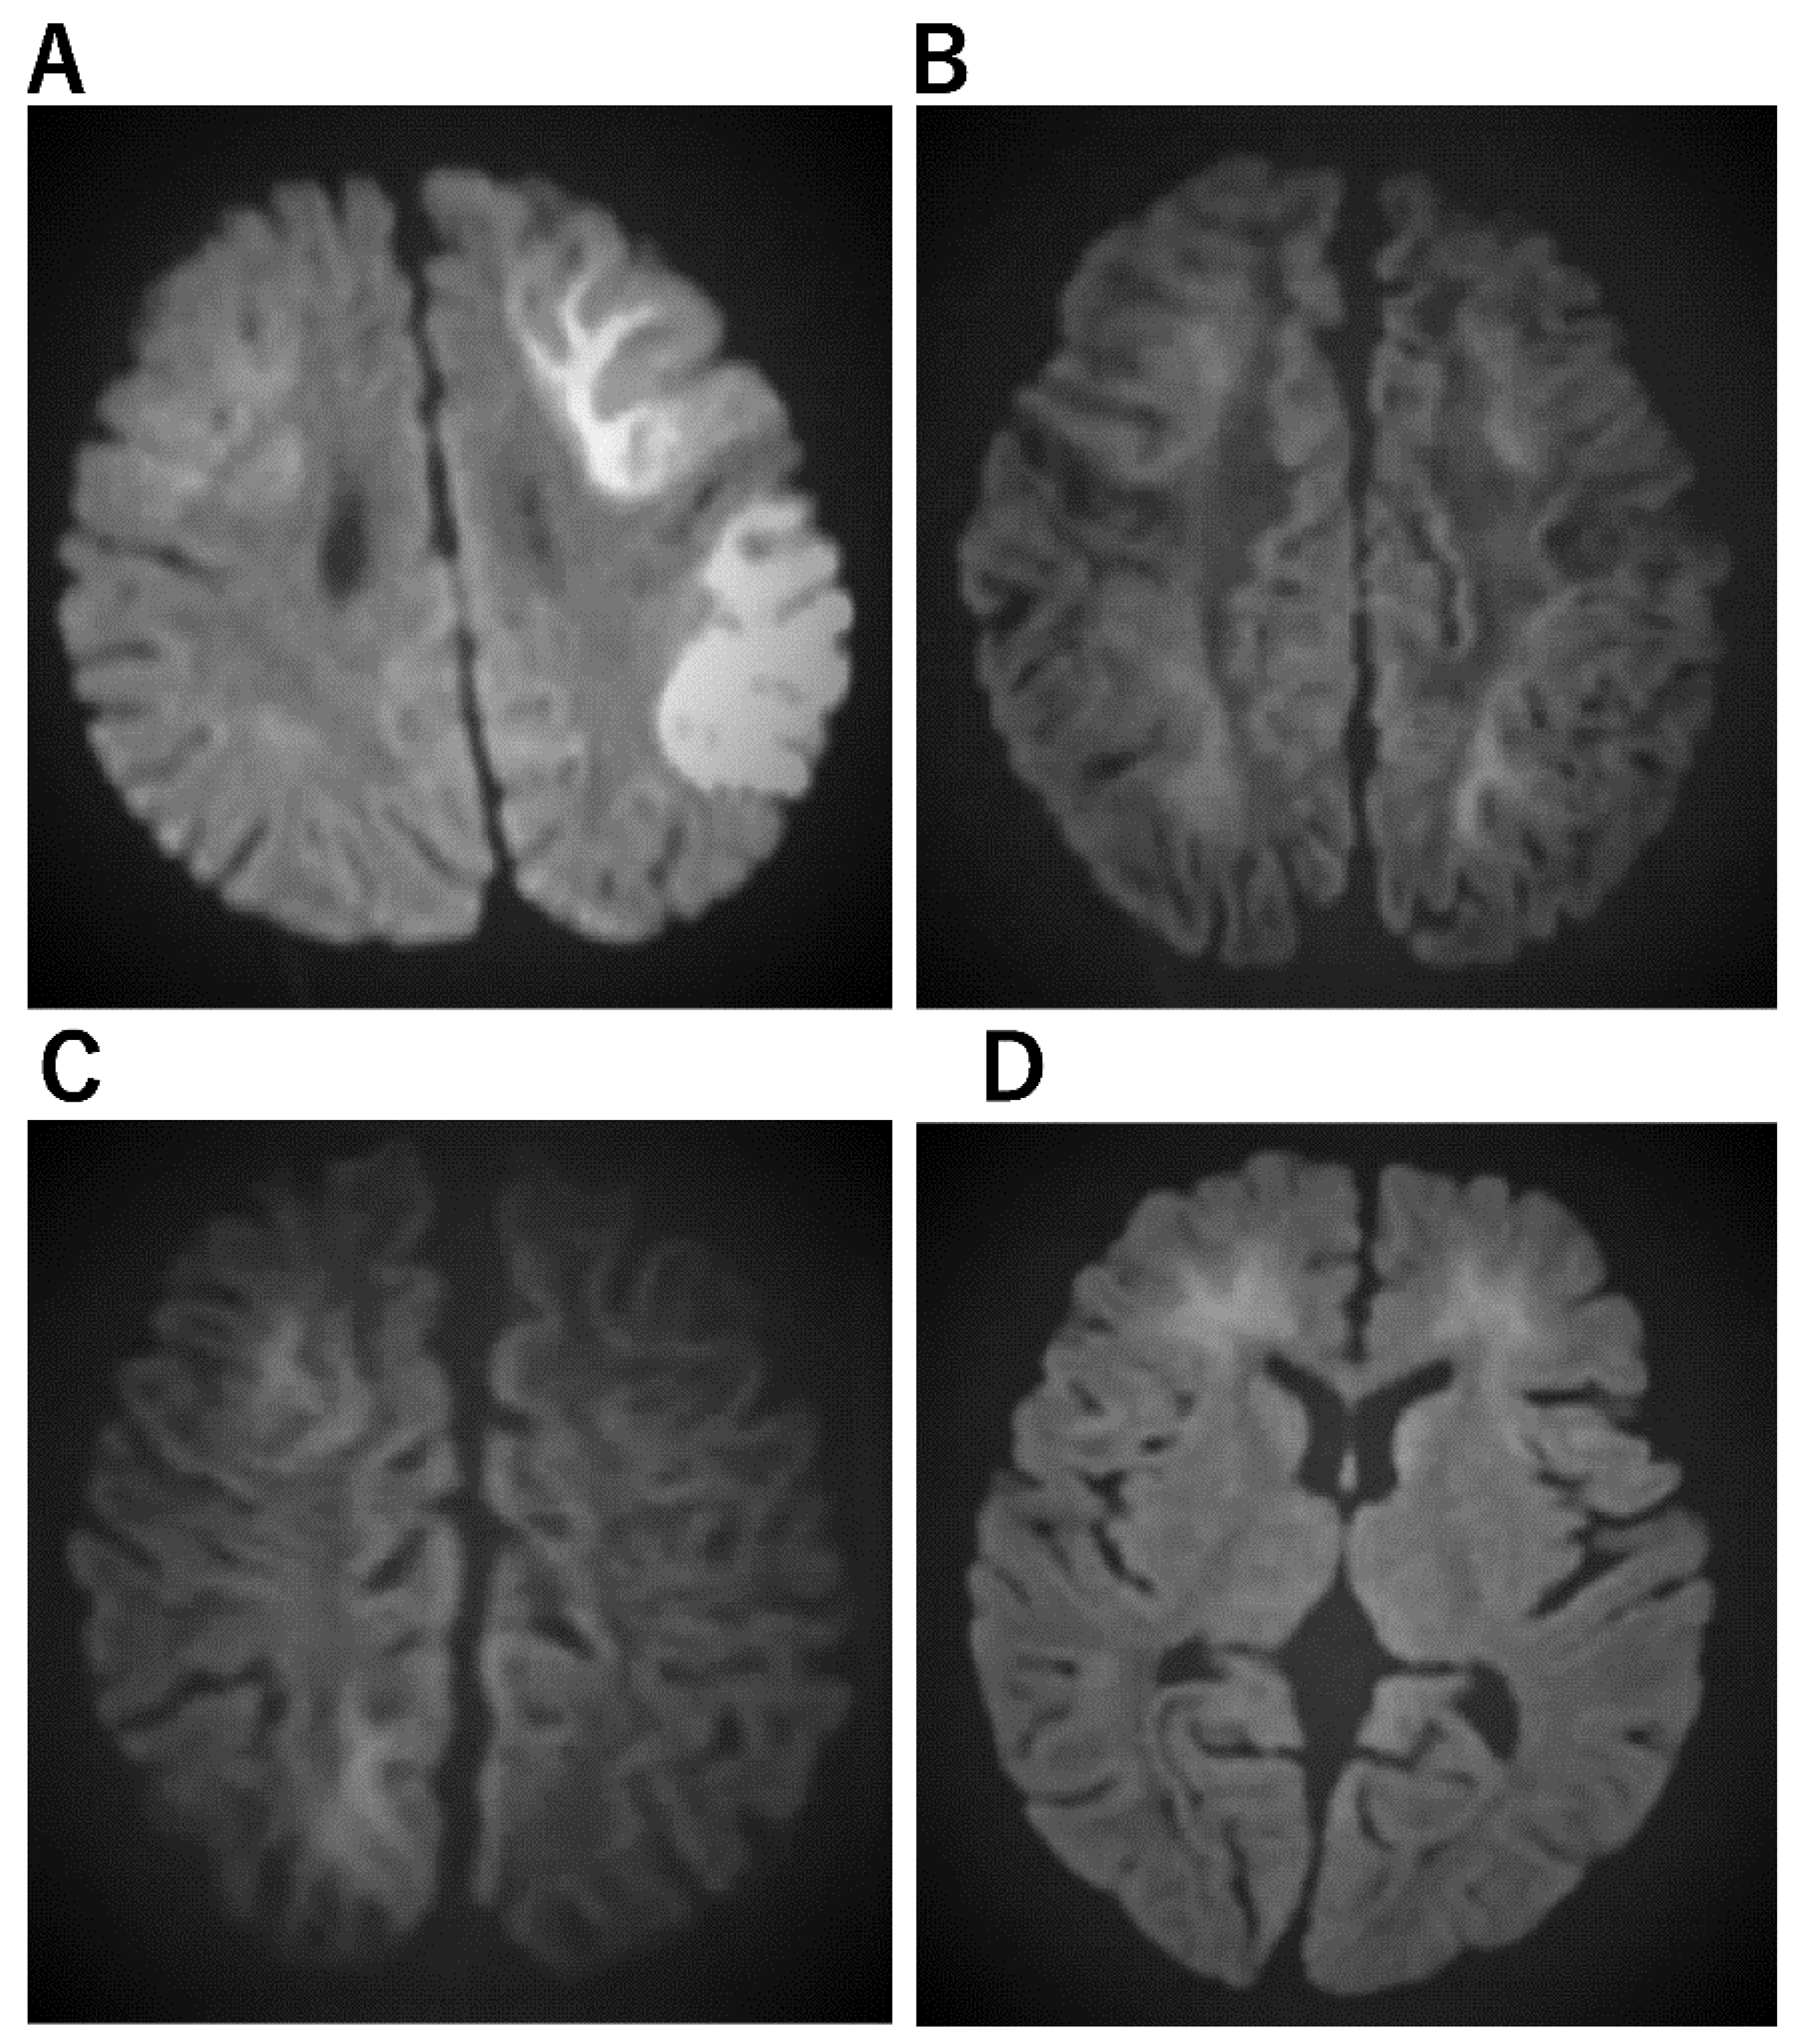

Figure 3. Imaging characteristics of AESD. (A) An 11-month-old boy who was admitted to the hospital with a high fever and 15 min seizure congestion of the right upper and lower extremities. The seizures stopped after the administration of midazolam. Thereafter, there was transient Todd’s palsy of the right upper and lower extremities. Brain MRI was normal. The fever resolved 3 days later and a rash appeared, which was clinically diagnosed as HHV-6 infection. The second diffusion-weighted brain MRI showed a bright tree appearance sign predominantly on the left side, diagnosing AESD. mPSL 30 mg/kg 3 days pulse therapy was administered. At the age of 6, he entered a regular elementary school, but his language skills were mildly poor. (B) A 3-year and 3-month-old girl. She has a 1 h febrile convulsion superimposed on fever. Midazolam brought the convulsions to a halt. The next day, she remained listless and was monitored with intravenous fluids; on the eighth day, she experienced a cluster of short convulsions in her limbs. Diffusion-weighted brain MRI revealed bilateral subcortical white matter predominance with bright tree appearance and an AESD diagnosis. Then, 48 h of mild cerebral hypothermia at 35.5 °C, steroid pulse therapy, and mitochondrial rescue therapy were performed. Six years after onset, she is living a normal fourth-grade elementary school life with no sequelae in terms of motor, language, or academic performance. (C) A 1-year and 7-month-old boy. After 4 days of febrile convulsive seizures, the fever subsided and a rash appeared; he was clinically diagnosed with HHV-6 infection. Multiple convulsive seizures lasting a few minutes were observed 5 days later. Slow waves were detected in the frontal and occipital regions of the EEG. Diffusion-weighted brain MRI showed an abnormally high signal in subcortical white matter and diagnosed AESD. mPSL pulse therapy and vitamin cocktail therapy were started. Body temperature was maintained at 35.5–36.0 TTM for 5 days The disease has been present for over two and a half years, and the child is now over 4 years old. There are no neurological sequelae and both language and motor functions are age-appropriate. (D) A 1-year-old boy with a fever of 39 °C and spontaneous convulsions that stopped spontaneously before reaching the hospital; 4 days later, he presents with two 3-min generalized convulsions and is rushed to the emergency room with no recovery of consciousness. He was admitted directly to the ICU, sedated with Rabonar, and given 48 h of mild cerebral hypothermia at 35 °C. Steroid pulse therapy was also administered. Thereafter, the temperature was kept at 36 °C, and the patient was transferred from the ICU to the general ward on the eighth day. On the same day, a brain MRI showed an abnormally high signal on diffusion-weighted images with bilateral frontal lobe predominance, and a diagnosis of AIEF-type AESD was made. Rehabilitation was continued until he was over 2 years old. After 1 year of onset, both his motor and language functions have recovered to the level of his age.